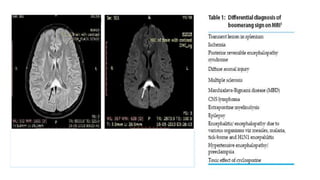

13

lentiform fork sign

• A bright hyperintense rim delineates the lateral

(external capsule, long arrow) and medial boundaries

(external medullary lamina [short arrow] and internal

medullary laminae [thin arrow]) of both putamina. The

globus pallidus is divided into 2 parts by the internal

medullary laminae, which can be seen in pathologic

conditions on MR images.

• Focal restricted diffusion seen

• Seen in – metabolic acidosis – AKI, metformin,

methanol, HHS